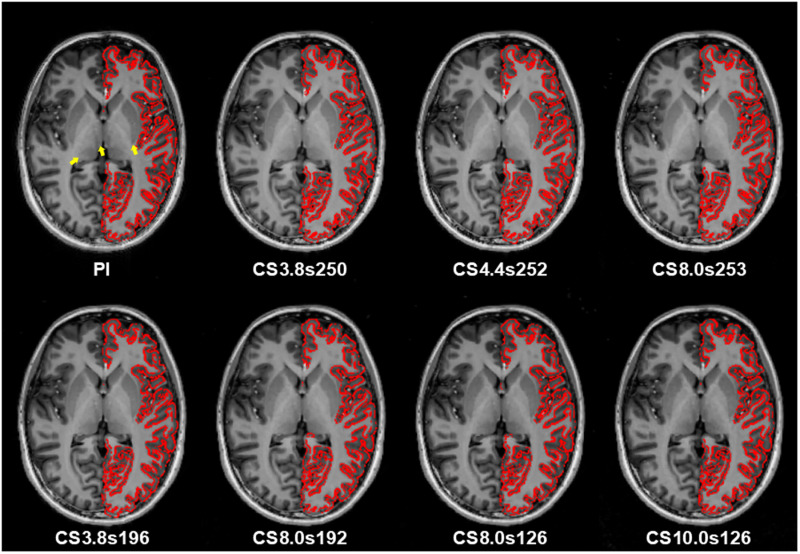

本研究的目的是系统评估压缩感知(CS)对超高场(UHF)下磁化制备的2快速采集梯度回波(MP2RAGE)的采集时间、图像质量、T1映射精度和分割一致性的影响。MP2RAGE序列采用CS和并行成像(PI)技术,即广义自校准部分并行采集(GRAPPA),具有不同的欠采样因子和每次重复时间(TR)的样本。评估了获取时间、T1映射的定量准确性和兴趣区域(roi)的分割一致性。与PI-MP2RAGE相比,CS-MP2RAGE的采集时间(< 3分钟)减少了61%,并保持了相当的图像质量、分割精度和t1映射保真度。尽管图像看起来与PI-MP2RAGE相似,但较高的采样不足系数有效地缩短了扫描时间,但引入了高达20%的分割体积不匹配并增加了T1值。减少每个TR的样本数量增强了图像质量,允许更高的欠采样因子而不会显着损失保真度,这一发现与先前的研究一致。然而,在复杂roi中,过低的采样密度会破坏重建的稳定性。我们的研究结果表明,CS-MP2RAGE在保持高图像质量和定量精度的同时显著缩短了扫描时间,使其成为超高频应用中GRAPPA的可行替代方案。欠采样因素和每TR采样之间的相互作用对于优化扫描效率至关重要。未来的研究应探索其在临床和研究中的应用。

The aim of this study was to systematically evaluate the impact of compressed sensing (CS) on acquisition time, image quality, T1 mapping accuracy, and segmentation consistency in magnetization-prepared 2 rapid acquisition gradient echo (MP2RAGE) at ultra-high fields (UHF). MP2RAGE sequences were acquired using the CS and parallel imaging (PI) technique, i.e., generalized autocalibrating partially parallel acquisitions (GRAPPA), with varying undersampling factors and samples per repetition time (TR). The acquisition time, quantitative accuracy of T1 mapping, and segmentation consistency across regions of interest (ROIs) were assessed. CS-MP2RAGE achieved a 61% reduction in acquisition time (< 3 min) compared with PI-MP2RAGE and maintained comparable image quality, segmentation accuracy, and T1-mapping fidelity. Higher undersampling factors effectively reduced scan duration but introduced segmentation volume mismatches of up to 20% and increased T1 values, despite the images appearing similar to PI-MP2RAGE. Reducing the number of samples per TR enhanced image quality, allowing for higher undersampling factors without a significant loss of fidelity, a finding consistent with previous studies. However, excessively low sampling densities destabilized reconstruction in complex ROIs. Our findings demonstrate that CS-MP2RAGE significantly reduces scan time while maintaining high image quality and quantitative accuracy, making it a viable alternative to GRAPPA in UHF applications. The interplay between undersampling factors and samples per TR is crucial for optimizing scan efficiency. Future studies should explore its application in clinical and research settings.